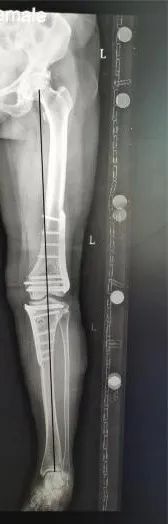

李阿姨术后膝关节外形,左下肢变直了

左下肢全长X线力线恢复